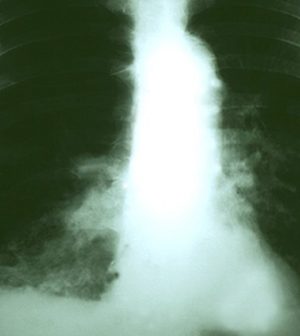

Cancer Drug Keytruda a New Weapon Against Advanced Lung Tumors

SUNDAY, June 3, 2018 (HealthDay News) — A cancer drug that boosts the immune system outperforms chemotherapy in fighting advanced lung cancer, a new trial shows.